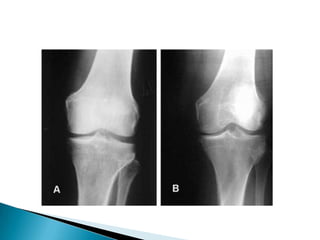

5) Manejo del Ultrasonido general en el diagnóstico de los reumatismos de partes blandas.6) Asesores en la utilización racional de métodos diagnósticos como resonancia o artroscopias e indicaciones quirúrgicas para pacientes reumáticos, que son prescritas con mucha mayor ligereza por parte de otros especialistas de áreas afines.7) Supervision y regulacion de la terapia física y ocupacional administrada a enfermos reumáticos.

5) Manejo delUltrasonido general en el diagnóstico de los reumatismos de partes blandas.6) Asesores en la utilización racional de métodos diagnósticos como resonancia o artroscopias e indicaciones quirúrgicas para pacientes reumáticos, que son prescritas con mucha mayor ligereza por parte de otros especialistas de áreas afines.7) Supervision y regulacion de la terapia física y ocupacional administrada a enfermos reumáticos.